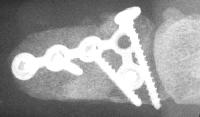

Late Xrays.